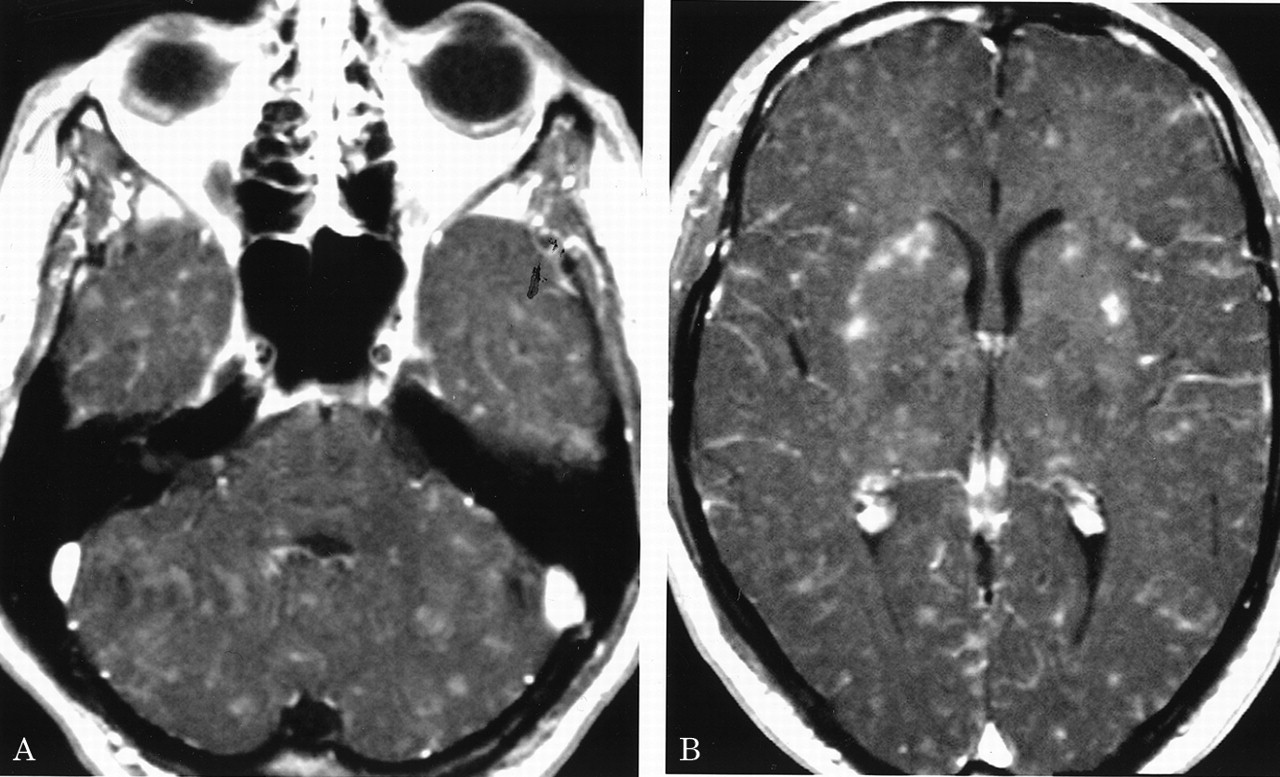

多病灶的幕上的白质病变,包括胼胝体(图1),在所有27个病人,有频繁的参与小脑,中间小脑总花梗,和脑干图1,表)。病变众多,往往是小(3 - 7毫米)但有些小病变成为支流和一些大的(> 7毫米)。19病人实质增强,当明显,导致大脑的粟粒状的外观(图2)。胼胝体的损伤通常是小的,并且涉及中央与周边的相对保留纤维;增强是变量。急性胼胝体的病变(图3)中观察到的活动脑病取而代之的是一个“充满”/穿孔先生出现在后续所有27例(图4),可能代表microinfarctions,没有出现在其他地方。胼胝体,最好在薄片(3毫米厚)矢状T1或T2矢状/质子密度加权图像,由一系列小(3毫米)中央孔相隔7毫米矢状T1和T2矢状/质子密度图像。这些扩展在整个长度的胼胝体。当急性(“雪球”)(见大图3)胼胝体的病变,慢性残余孔较大,尤其是在压部。线性缺陷有时看到的,可能反映microinfarction间接辐射在胼胝体轴突。中央孔(见图4)被认为是由于横向辐射的胼胝体轴突的微型心肌梗塞的可能性。

有深的灰色基底节和丘脑病变19病人(参见表),通常体现在T2信号强度增加,质子密度,和天赋的图像。大病变类似“巨大陷窝”43并建议纹状体外动脉增的广泛参与。三个这样的病人显示这些病变显著增强,伴随着leptomeningeal增强。实质增强(见图2)有关的大脑区域,偶尔与leptomeningeal增强(见相关表)。串行扫描被执行,增强可能是更常见。脑病减弱和病人开始恢复,只有残余病灶中央(见胼胝体的洞图4)和一些白质病变。在两个病人,增加信号强度变化在胼胝体伴随着中央胼胝体的洞在最初的MRI检查。更严重影响病人、脑和小脑萎缩随之而来。在两个这样的实例,胼胝体越来越萎缩,前面提到的胼胝体的洞几乎消失了。

在一些患者中,白质变化是最小的程度与严重程度的脑病。双倍剂量与磁化钆转移可能显示(见更广泛的变化图2),这将有助于解释这个明显的临床/差距先生。我们使用这个序列只在我们的一个病人,然而。